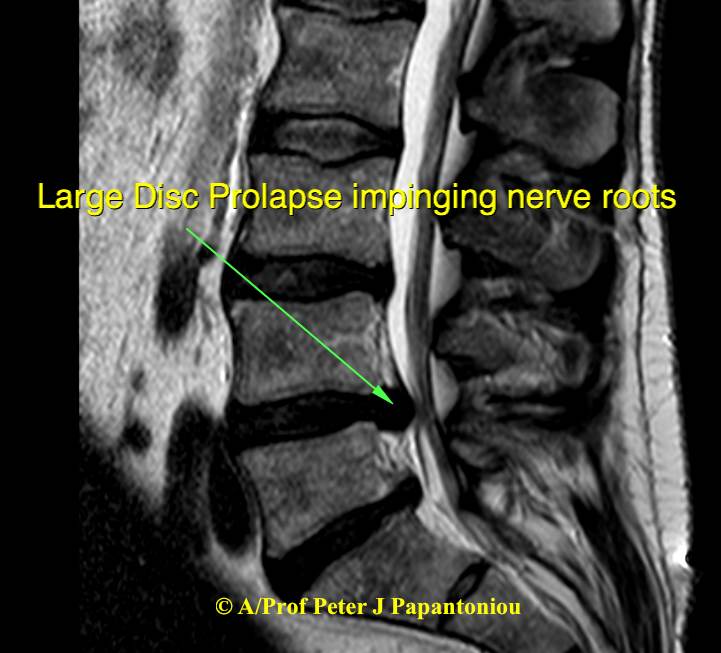

Disc Prolapse

A disc prolapse, also known as a herniated disc or slipped disc, occurs when the soft, spongy material (nucleus pulposus) inside a spinal disc bulges out through a crack in the tougher exterior (annulus fibrosis). This can put pressure on nearby nerves, causing pain and other symptoms such as tingling or numbness in the limbs.

A lumbar discectomy is a surgical procedure to remove part of a damaged or herniated disc in the lower spine. It is typically done to relieve pressure on a spinal nerve, reducing pain, numbness, and weakness, often caused by sciatica.